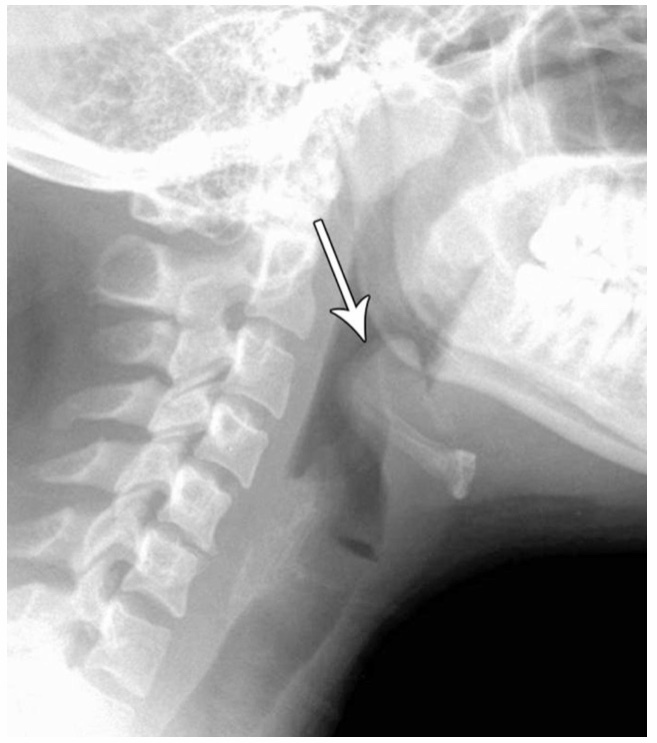

This pediatric disease process is represented by a “thumbprint” sign on X-ray.

EPIGLOTTITIS

THIS X-RAY IS A SIGN OF WHAT IN PEDIATRICS?

CROUP